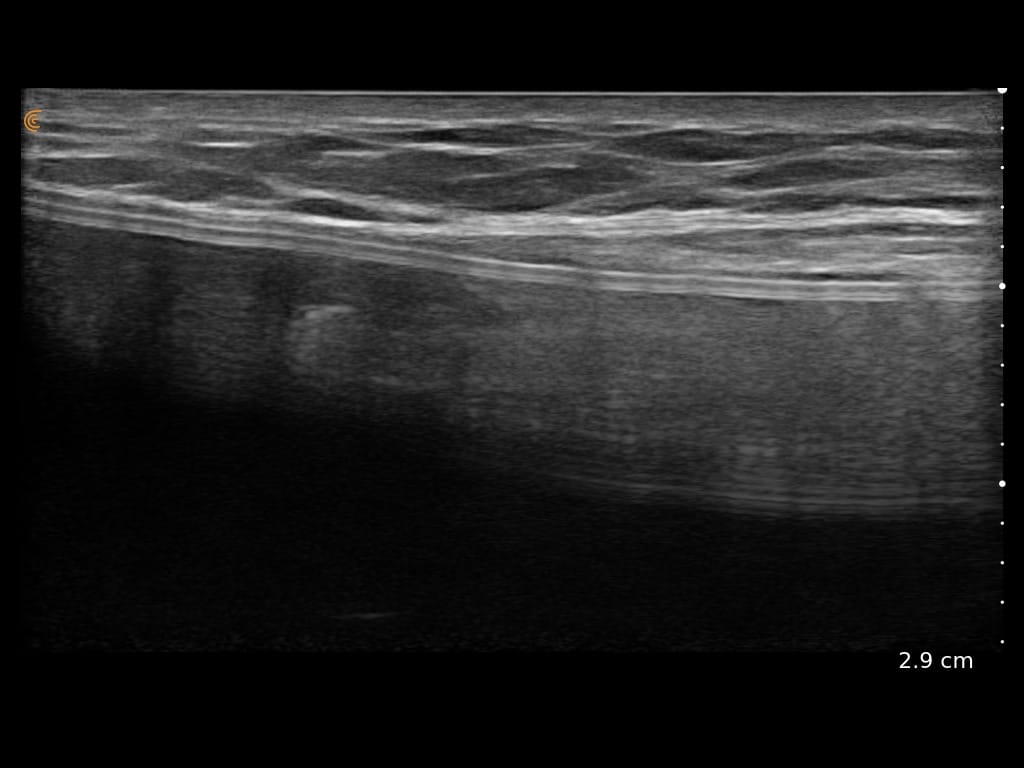

Ultrasound Imaging is very useful clinical tool to assess patient’s anatomy. In the past, ultrasound imaging was done primarily by radiologists, but is now being employed by many clinical specialties. Ultrasound use by Plastic Surgeons, however, is relatively new. Dr. Wigod has found ultrasound imaging to be a particularly valuable addition to physical exam and provides this service to his patients. Ultrasound imaging is especially useful to assess breast implants for problems such as ruptures, capsular contracture, and fluid collections. Dr. Wigod also uses ultrasound to examine other body areas and to help guide nerve blocks. Surgeon performed ultrasound does not replace radiologist performed imaging and is not for cancer screening.